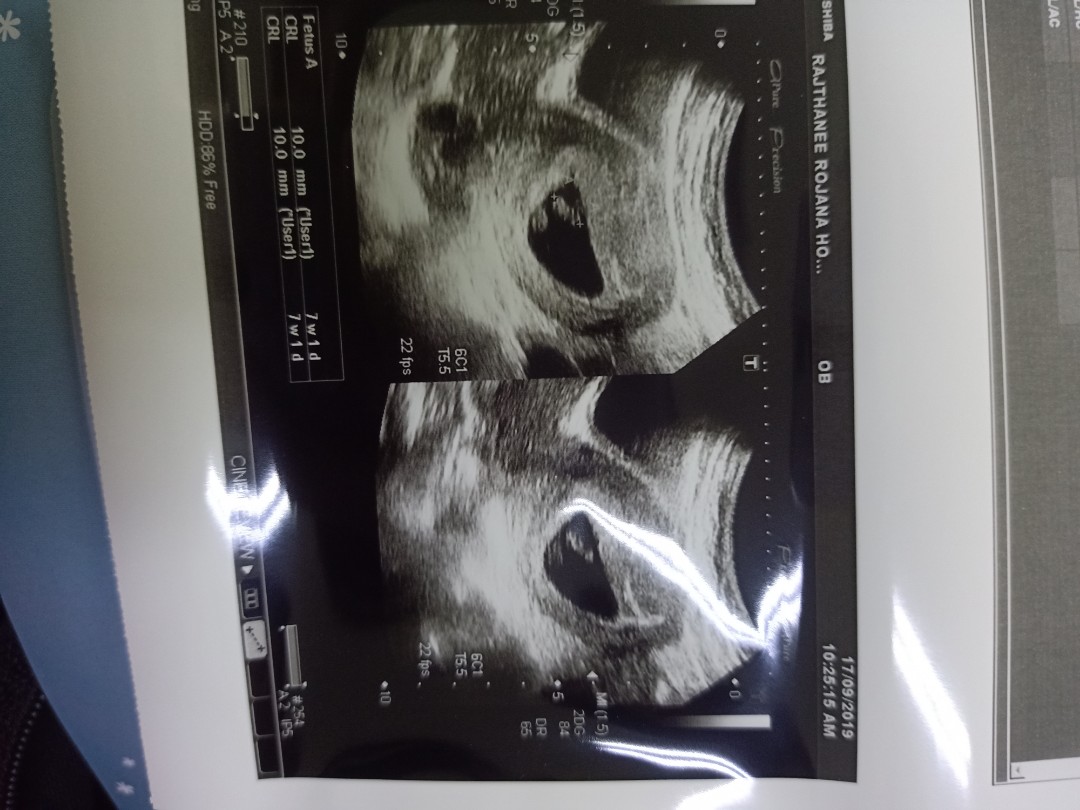

ซาวด์เจอถุงครรภ์7W4Dค่ะแต่ยังไม่เจอตัวเด็กอยากทราบว่าคุณแม่ท่านไหนเจอตัวเด็กกันกี่Wบ้างค่ะ

7w1d เจอตัวน้องแล้วค่ะ เห็นหัวใจเต้นด้วยค่ะ